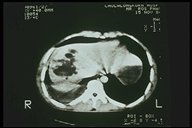

Combined severe liver injury and splenic hematoma, intraperitoneal bleeding is also noted

TAfter conservative treatment of even severe liver injury with stable hemodynamic status, the liver resolutes very well (CT three weeks after injury)